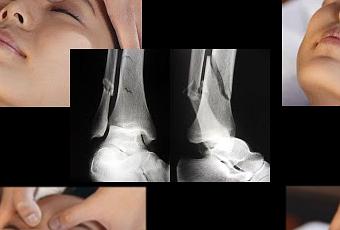

Existe una amplia gama de opciones terapéuticas orientadas a prevenir

fracturas en personas de edad avanzada. El grupo con mayor riesgo de presentar

este tipo de lesiones lo comprenden las mujeres postmenopáusicas, debido a que

la disminución en la producción de estrógeno altera el metabolismo del hueso y

ocasiona debilidad en los mismos. Al respecto, la doctora Ytzel Pérez Angulo,

internista y especialista en metabolismo mineral óseo, y profesora de clínica

médica en la Universidad de Carabobo, comentó que recientemente un

grupo científico de la Organización Mundial de la Salud, desarrolló un

algoritmo denominado FRAX, que calcula el riesgo de fractura con una antelación

de 10 años. Este sistema toma en cuenta diversos factores de riesgo, tales

como: edad, género, densidad mineral ósea del cuello femoral, índice de masa

corporal, historias previas de lesiones de esta clase, tabaquismo, ingesta

alcohólica, uso de glucocorticoides, osteoporosis secundaria, artritis

reumatoidea e historia familiar de fractura de cadera en padres. Estos datos

permiten determinar mejor un tratamiento específico e individual para cada

paciente, según su riesgo de fractura, además de predecir quien tiene más

riesgo de presentar esta clase de lesión. De esta manera, se pueden establecer

tratamientos más agresivos para disminuir esa posibilidad. Por lo general el 60%

de las personas que reciben tratamiento con bifosfonatos orales de uso semanal

y 80% de quienes usan dicho medicamento diariamente, abandonan el

tratamiento durante el primer año. El ácido zoledrónico de 5 miligramos tiene

la ventaja de ser un medicamento de administración anual endovenosa, que facilita

enormemente la adherencia al tratamiento. Además, permite una reducción

sustancial del riesgo de fractura, tanto vertebral como de cadera; de

esta forma, mejoramos la calidad de vida del paciente.